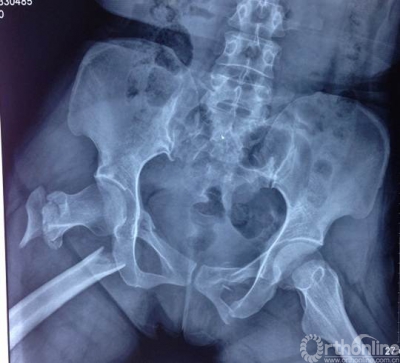

肖XX,男,35岁

术后

术后1年